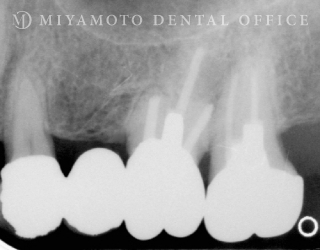

症例15

リグロス®を用いた歯周組織再生療法(根分岐部)+歯内療法

1. 治療前

2. 治療後